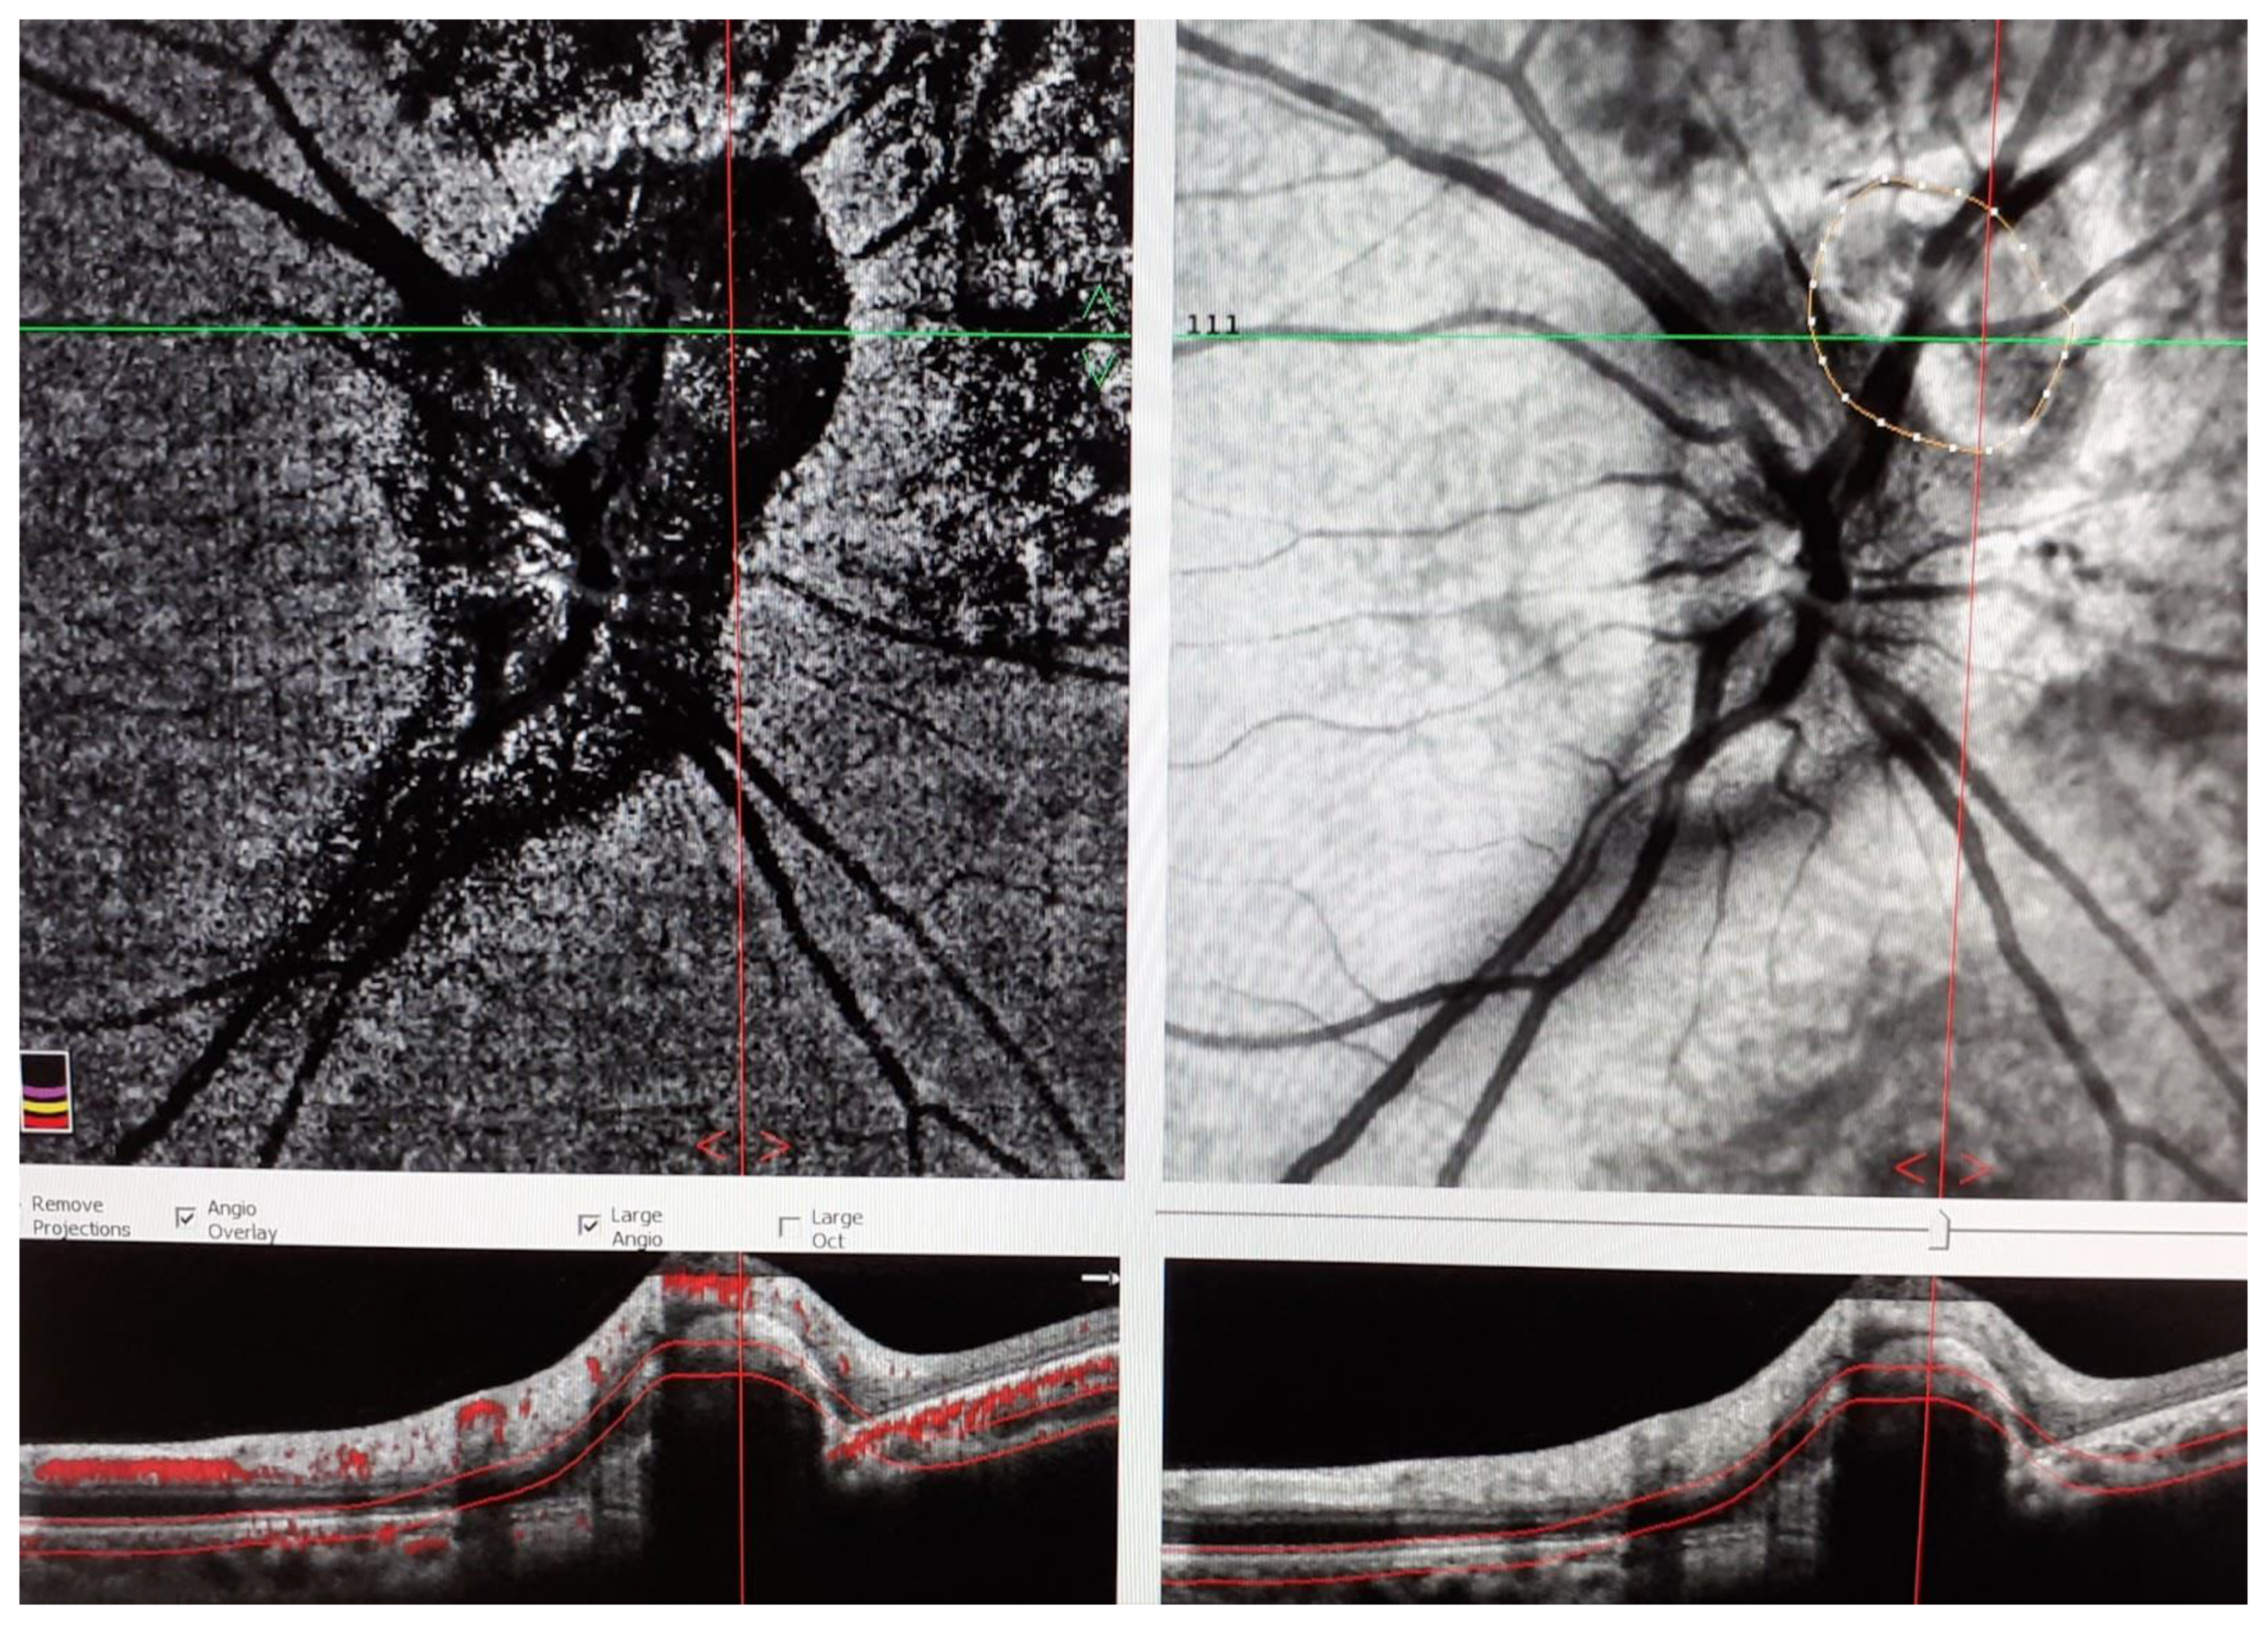

2. Case Presentation